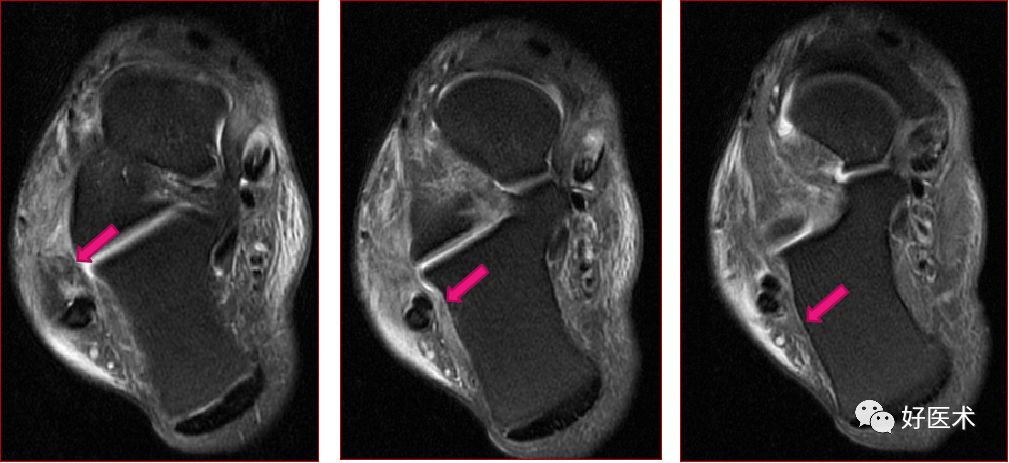

跟腓韧带

跟腓韧带急性完全撕裂